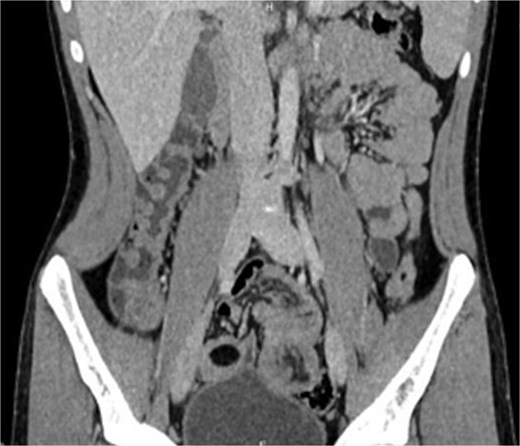

Emergency laparotomy revealed a jejuno-jejunal intussusception 60 cm distal to the ligament of Treitz (Fig. 3). Manual reduction exposed a compound ileo-ileal intussusception without vascular compromise (Fig. 4). The intramural lipoma was subsequently identified (Fig. 5). Resection and end-to-end anastomosis of the involved ileal segment, with a 5-cm safety margin on each side, were performed.

Preoperative view of manual reduction exposed a compound ileo-ileal intussusception without vascular compromise.